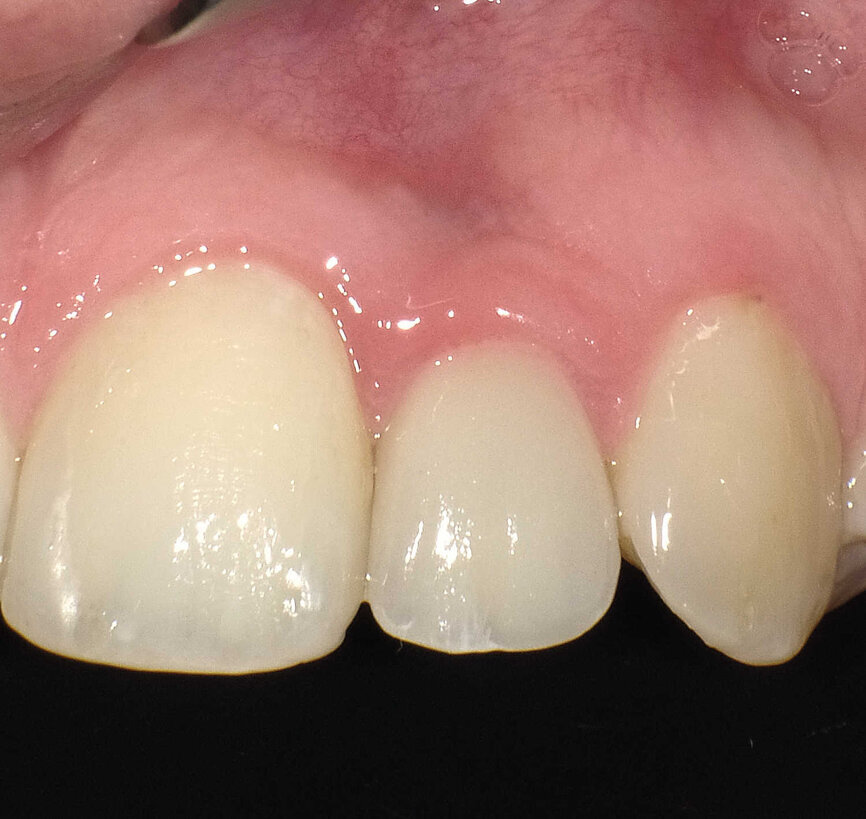

Fig. 9 : Contrôle intraoral de la couronne et du tissu mou périphérique après trois ans. À noter : la stabilité des papilles, soutenues par l’os formé sur l’épaulement incliné.

L’implant a été mis en place au moyen d’un instrument spécial pour l’insertion d’implant, qui permet au praticien de pousser l’implant fermement, en appliquant une pression précise dans l’ostéotomie (Fig. 5). La dernière étape a consisté à introduire complètement l’implant au moyen du maillet, et de l’instrument d’insertion fixé à la poignée de serrage droite. L’implant étroit était dès lors bien positionné entre les deux racines (Fig. 6). L’implant de 8 mm de long et de Ø 3 mm a été inséré par l’application d’une pression dans l’ostéotomie, et l’utilisation du maillet et de l’instrument d’insertion à 3 mm sous le niveau de l’os crestal (Fig. 7). La seconde phase du traitement a été réalisée après six mois de cicatrisation et a consisté à désenfouir l’implant. Un pilier ayant un corps de Ø 2 mm et une base hémisphérique de Ø 4 mm a été choisi pour connecter les couronnes provisoires à l’implant. Il est important de veiller à la bonne cicatrisation du tissu mou autour du contour coronaire adéquat, et celle-ci peut être obtenue par une modification du profil d’émergence de la couronne provisoire jusqu’à la formation des papilles. Après la cicatrisation complète du tissu mou, la dernière empreinte a été prise et la couronne définitive a été scellée sur le pilier en titane (Figs. 8 et 9).